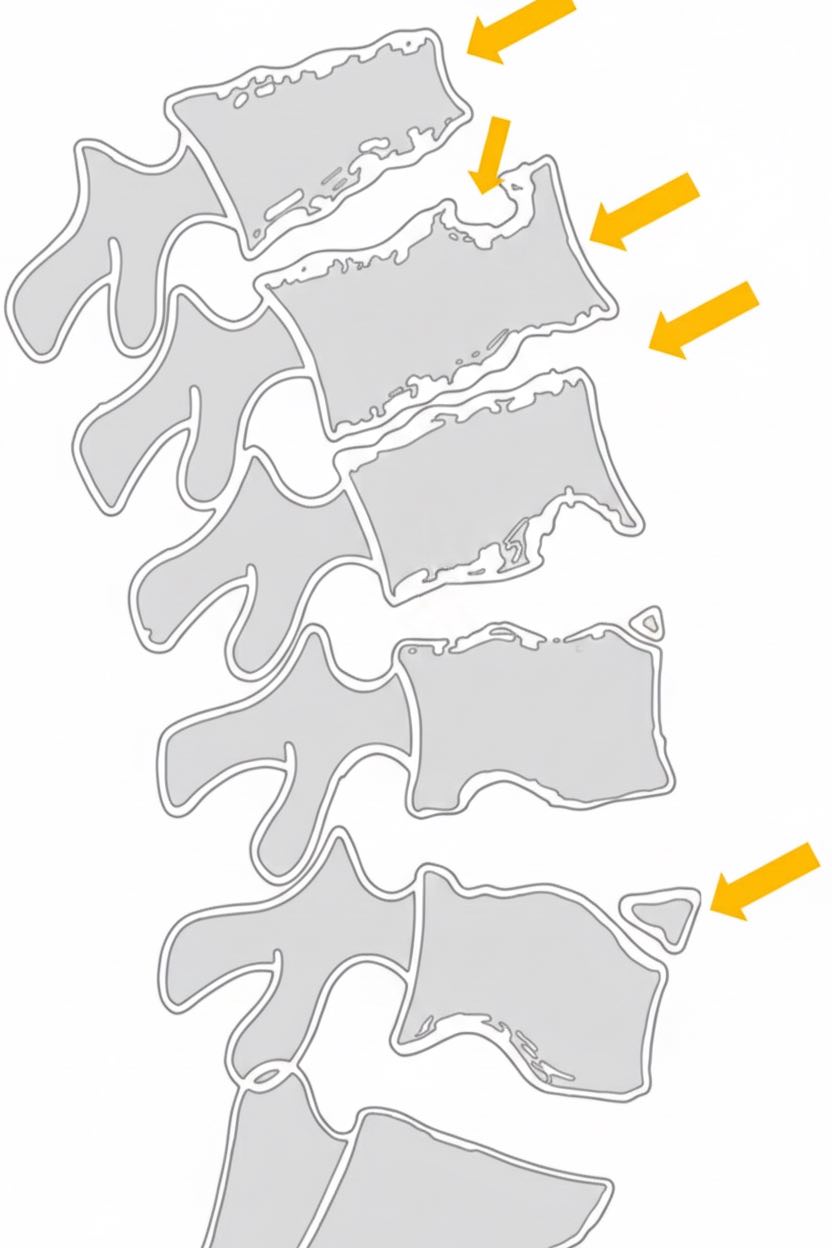

Distrophie rachidienne de croissance = ado avec cyphose > 45° ± douleurs

- cunéïformisation vertébrale

- irrégularité des plateaux vertébraux

- élargissement antéro-postérieur

- pincements intersomatiques

- atteinte listels marginaux antérieurs